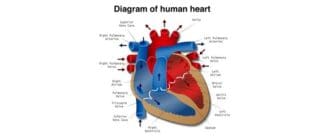

ハートブロック、AVバンドル、またはバンドルブランチブロックは、心臓の電気システムに影響を与えます。心臓の血管に影響を及ぼす冠動脈疾患とは異なります。 心臓ブロックでは、心臓が通常よりも不規則かつゆっくりと鼓動し、一度に […]